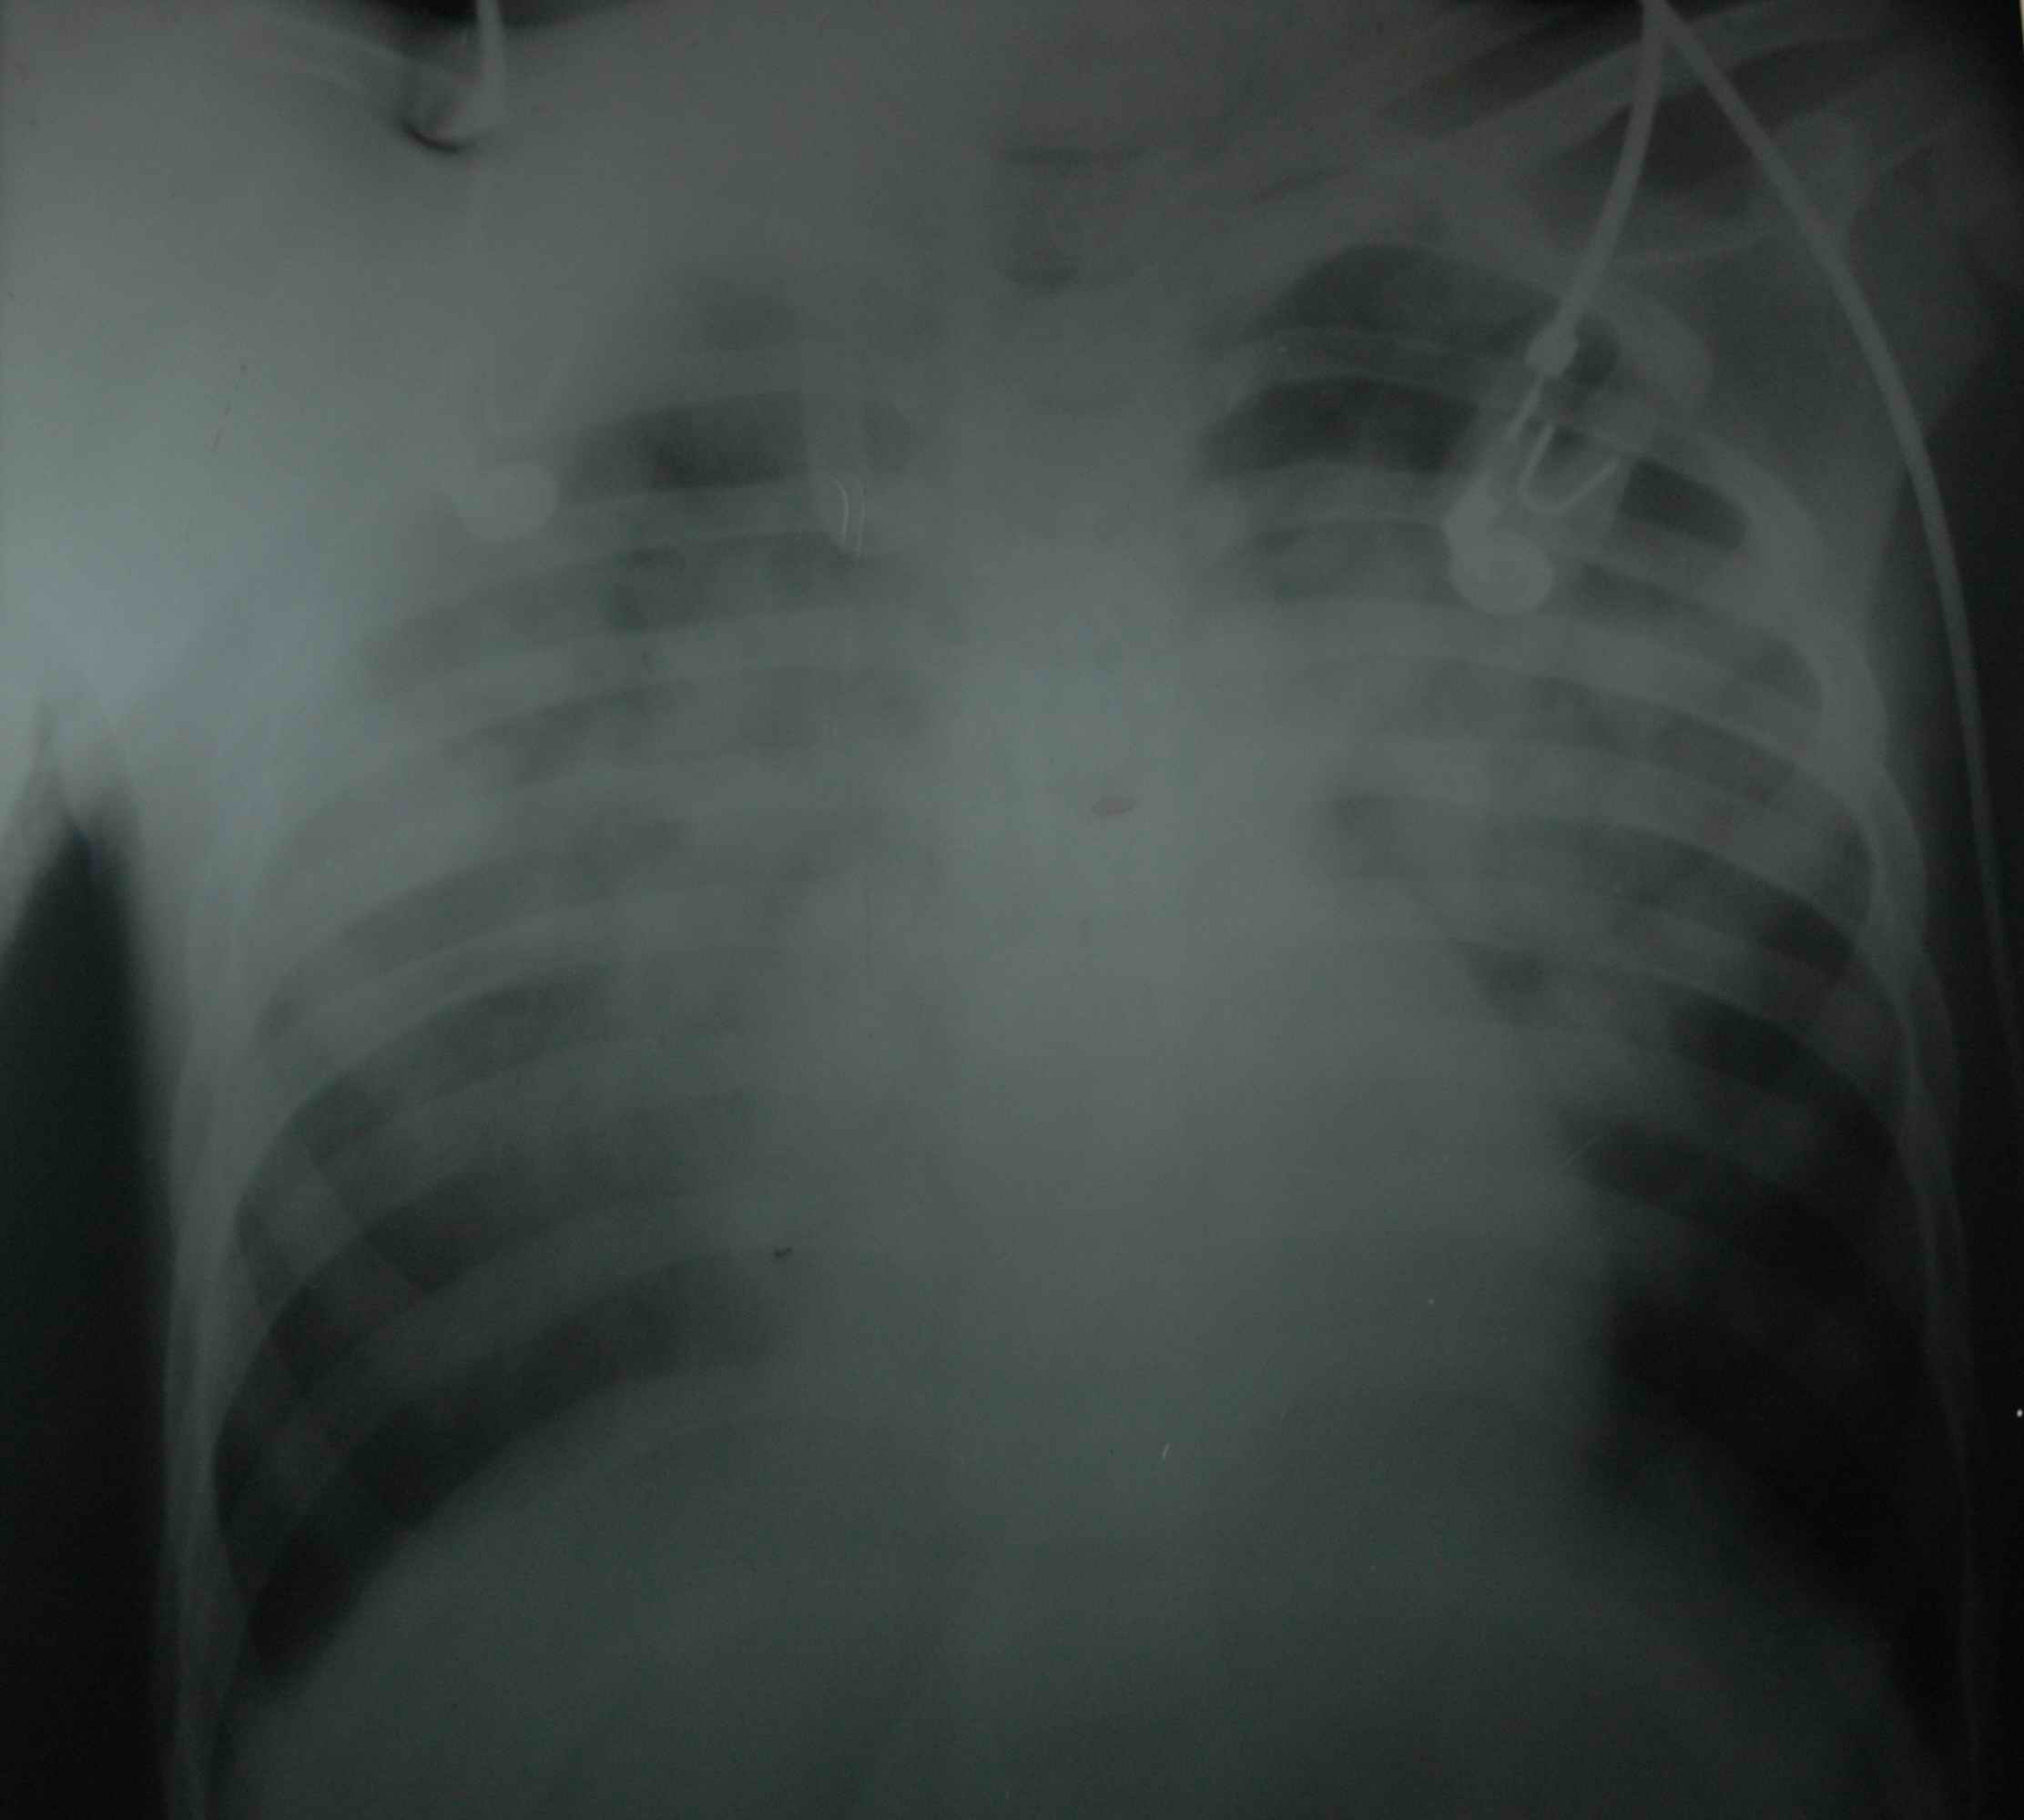

![]() |

A. Recently scorpion antivenin has become available, but in my experience it does not work if it is administered after one hour of the sting (JAPI 2008). Moreover it is expensive. A 10 ml vial costs 350 INR (Indian Rupees), and you need to give 5 to 10 vials (to be administered by intravenous route). This comes to about 3500 INR for the treatment of just one patient. Just compare this with Prazosin, which costs INR 2 only. Prazosin is used in Turkey (J Amer therapeutic 2007) and Saudi Arabia (Saudi medical J 2008) . Thus Prazosin can rightfully be called a poor man antivenin ( JAPI 2008).